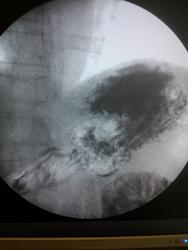

Пациент, 60 лет. На ФГДС: В антральном отделе отмечается некоторая ригидность на малой кривизне, рядом с привратником.

Не вижу изменений в антральном отделе, но обращает внимание некоторая ригидность задне-медиальной стенки субкардиально.

Обратила внимание на уплощение контура на малой кривизне препилорического отдела. Но только на одном снимке, на остальных - без особенностей. Вряд ли стоит придавать этому значение. Вы видели моторику - Вам судить